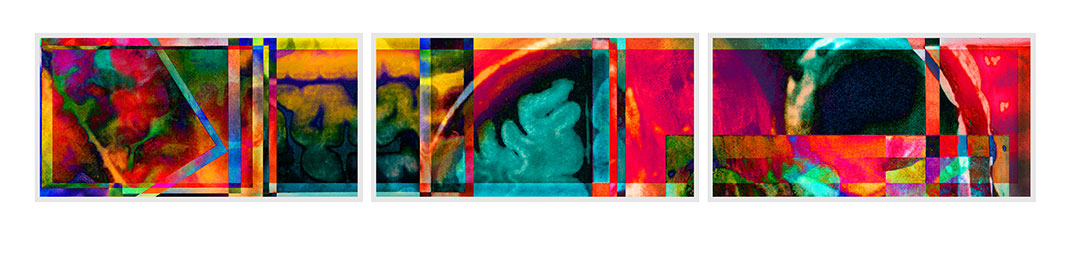

Elle trouve alors sa source d’inspiration dans sa maladie à travers ses IRMs. « Mes nombreux traitements m’ont donné envie de réinterpréter l’imagerie médicale. Les patients, souvent anxieux, ne voient que laideur et effroi dans les pixels noirs et gris des IRMs. J’ai alors ressenti le besoin vital de les utiliser pour montrer les merveilles et la beauté de nos cerveaux, y compris ceux souffrant d’une maladie. Je veux guérir les patients de la peur de regarder leurs IRMs », s’émeut Elizabeth.

En réutilisant ses scanners, Elizabeth Jameson cherche à insuffler des émotions et des sentiments dans la froideur technologique. Pour cela, elle utilise de nombreux supports : la peinture sur soie ou encore des impressions à partir de gravures sur cuivre ou sur plaque solaire. Ensuite, elle renforce la couleur de ses images grâce à de la peinture, des crayons ou du pastel sec. Le résultat offre une collection brillante, colorée, pleine d’émotion et de symbole.

Son travail est désormais connu à l’international. Certaines de ses oeuvres font partie des collections permanentes de l’Institut national de la santé (université Stanford), de l’université Yale, de l’université Harvard, de l’université de Californie (Berkeley) et bien d’autres. Ses créations sont publiées régulièrement dans de nombreuses revues scientifiques.